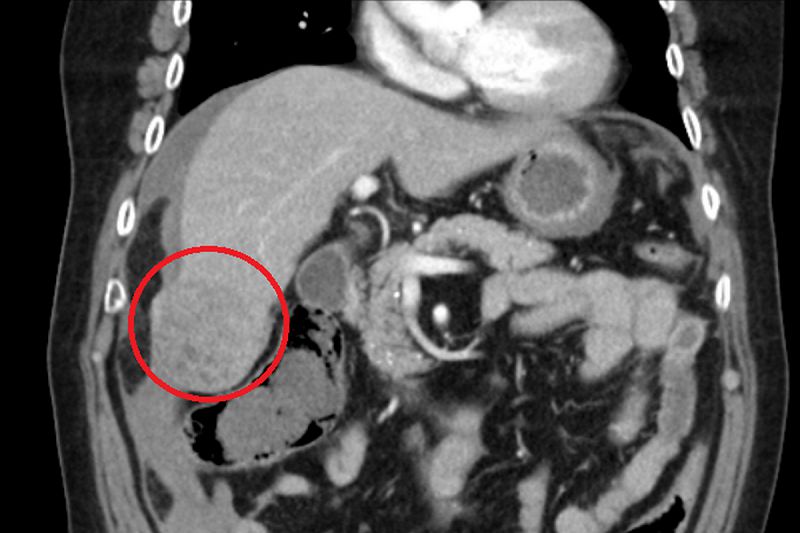

70歲的林爺爺五個月前因劇烈腹痛來到台北慈濟醫院求治,電腦斷層檢查發現其肝臟有一5公分大腫瘤且出現破裂情形,遂會診一般外科陳昱天醫師,後續進行抽血及超音波檢查確認腫瘤未轉移,診斷為早期肝癌,入住加護病房觀察。由於林爺爺與太太相依為命,沒有工作,考量經濟壓力,起先婉拒所有治療方案,所幸在醫師、專師、護理師及社工師不懈協調下,最終由陳昱天醫師執行手術,將腫瘤及周邊組織切除,術後林爺爺恢復狀況良好,五天後平安出院。

肝癌的診斷除了結合臨床表現外,還需藉由抽血檢查檢驗肝功能狀態,並利用腹部超音波、電腦斷層或核磁造影確認腫瘤型態、大小以及是否有轉移。化學治療、放射線治療、標靶藥物治療及手術治療等都是現今肝癌的治療選擇之一,手術治療方面,有腹腔鏡微創手術、達文西機械手臂手術及傳統開腹手術等方式,腹腔鏡手術及達文西手術是利用在腹部開一些小傷口深入肝臟處,在影像系統的輔助下進行切除;後者則是從病人右上腹劃開約20公分傷口,並同樣將病灶切除。陳昱天醫師表示:「兩者手術的差別在於傷口大小,病人疼痛感會有所不同,恢復速度也不一樣,而手術安全性則是相當,但須注意病人的心肺功能是否足以負荷手術。」而腫瘤切除後,肝臟會產生生長因子、細胞激素、賀爾蒙等,刺激肝臟內細胞的複製和增生,有助於復原,因此術後的營養攝取尤為重要。